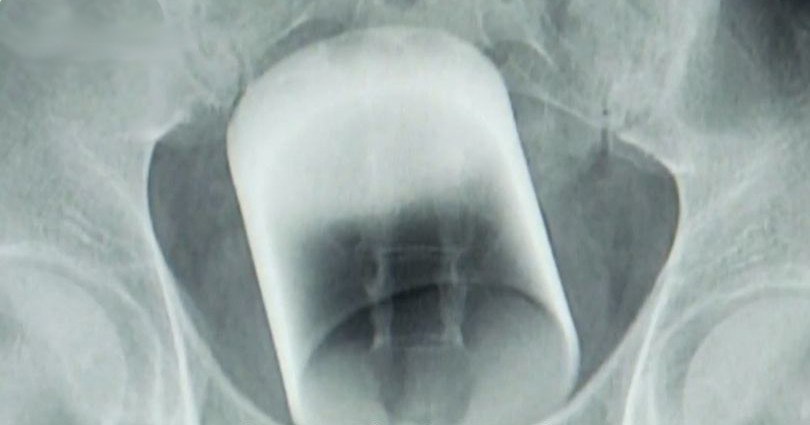

Поняв, что без медицинской помощи не обойтись, друзья приняли решение вызвать скорую помощь. Прибывшие медики были, мягко говоря, удивлены, обнаружив причину вызова. После оказания первой помощи, Дмитрия госпитализировали. Врачи провели необходимые обследования, чтобы оценить степень повреждений и разработать план дальнейших действий. Извлечение стакана потребовало проведения сложной медицинской процедуры.

Врачи отметили, что подобные случаи, хотя и довольно редкие, все же встречаются в медицинской практике. Они подчеркнули важность своевременного обращения за медицинской помощью в подобных ситуациях, чтобы избежать серьезных осложнений, таких как повреждение стенок кишечника, кровотечения или инфекции.